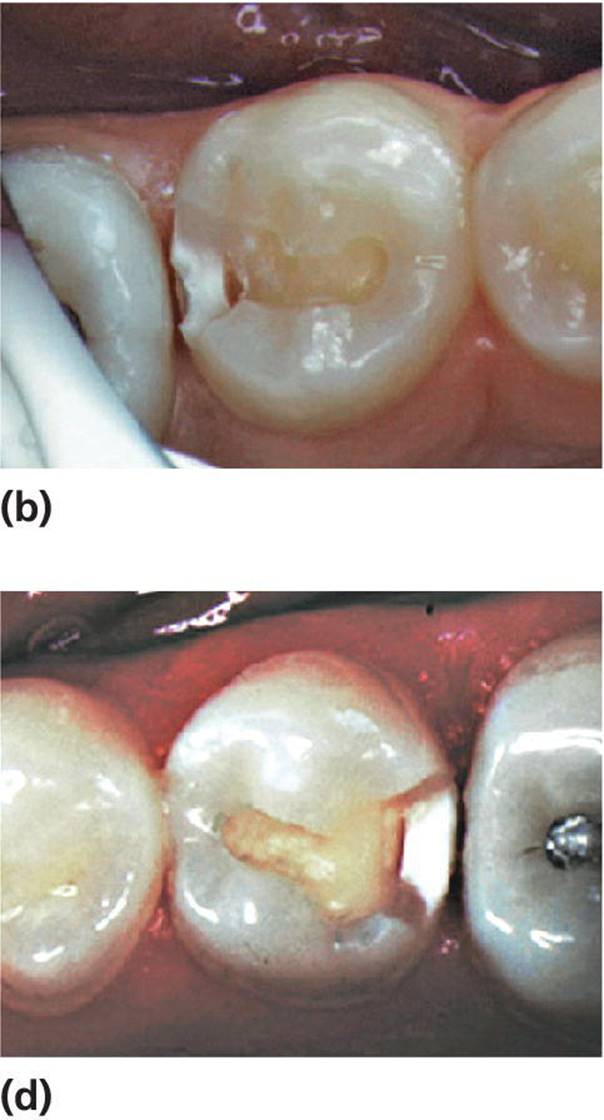

Assessment of lesion activity is as important as lesion detection. Criteria for active and inactive caries lesions slightly modified after Nyvad et al. [7] and Ekstrand et al. [8] are presented in Box 12.3. Figure 12.3illustrates active and arrested lesions.

Figure 12.3 Active and inactive/arrested caries lesions. Upper row shows initial (noncavitated lesions) and the lower row shows cavitated lesions. (a) Active noncavitated lesions close to the gingival line on the buccal surfaces of primary upper incisors in a 2‐year‐old. There is loss of luster and the lesions are rough on probing. (b) Arrested noncavitated lesions on the buccal surfaces of primary upper incisors in a 4‐year‐old. The lesions are situated at a distance from the gingival line, and are shiny and hard on probing. (c) Active cavitated lesion in a primary lower second molar in a 5‐year‐old. The dentin is soft on probing and the cavity borders are blunt and irregular. (d) Inactive/arrested cavitated lesion in a primary lower first molar in a 7‐year‐old. The dentin is brownish‐black, hard on probing, and the cavity borders are sharp and regular.